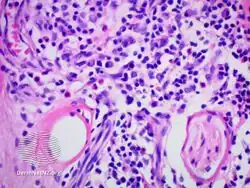

- IgG4-related skin disease pathology